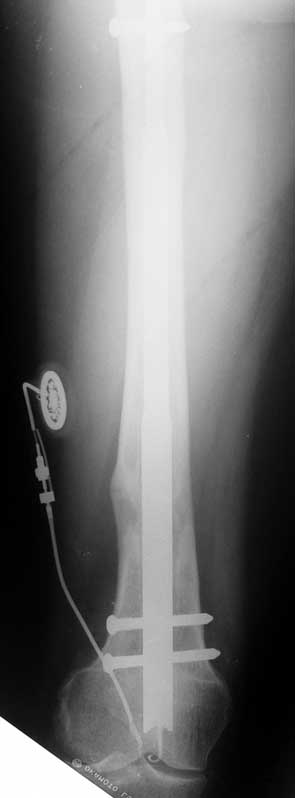

Since 2005 Dr. Mehmet KOCAOGLU is the first most Fitbone operating surgeon in TURKEY. He established the center of excellence for Fitbone surgeries in Istanbul. Fitbone comprises a telescopic nail implant that can extend, powered by an electric motor and controlled by a receiver with an antenna that is buried under the skin; the receiver in turn is controlled by a hand-held radio-frequency transmitter. The procedure for lengthening the lower leg is as follows:

A two-centimetre incision is made at the patient’s knee, and a rimmer is used to create enough space in the bone for a stainless steel nail.

The bone is cut about 14 cm below the knee from the inside with an internal saw. The stainless steel nail is held in place by two screws. The top of the nail is attached to a tiny, plastic-encased receiver that is placed under the skin. The patient controls the lengthening process. By pushing a button on the transmitter when it is placed against the antenna, the built-in motor extends the nail one millimetre per day. When the leg has grown to the desired length, lengthening stops, and the bone is allowed to solidify. The device can be removed about two years after the initial surgery. This procedure, however, comes at a price. While the Ilizarov external fixator costs approximately USD$4,000, and the ISKD implant about USD$8,000, the Fitbone device carries a price tag of roughly USD$15,000 (all prices exclusive of surgery costs).